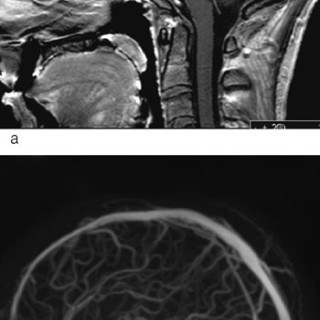

Den første detaljerte beskrivelsen av cerebral venetrombose, også kalt sinusvenetrombose, ble forfattet av Ribes i en artikkel fra 1825 (1). Siden fulgte en rekke kasuistikker basert på autopsimaterialer, som førte til den oppfatning at cerebral venetrombose representerte en sjelden, alvorlig sykdom karakterisert med hodepine, papillødem, epileptiske anfall, fokale utfall, progredierende koma og død (2, 3). Introduksjon av moderne nevroradiologisk utredning har gjort diagnostisering intra vitam mulig, dermed er det blitt klart at sykdomsutviklingen ved cerebral venetrombose heller sjelden er i...